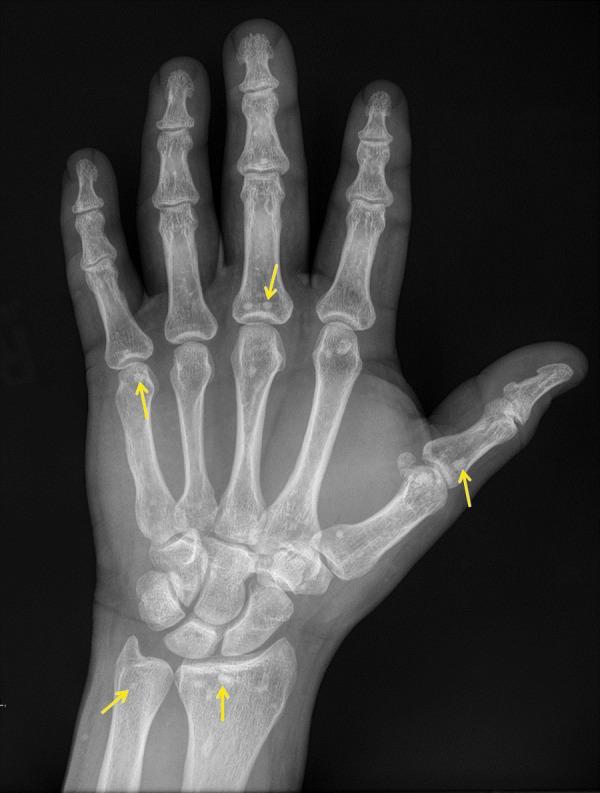

Osteopoikilosis is a rare condition that is characterized by multiple small non-aggressive appearing sclerotic foci in a periarticular distribution. Typically, it does not cause any symptoms and is diagnosed incidentally on imaging studies done for other reasons. We present a case of osteopoikilosis in a 37-year-old male, which was diagnosed incidentally on radiographs.